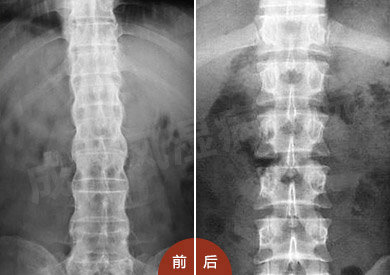

检查结果:脊柱X线显示其骨质遭到破坏,胸腰椎和颈椎间小关节间隙模糊;红细胞沉降率为66mm/h,C反应蛋白(CRP)为45mg/l 。

(图:治疗前后脊柱X线片)